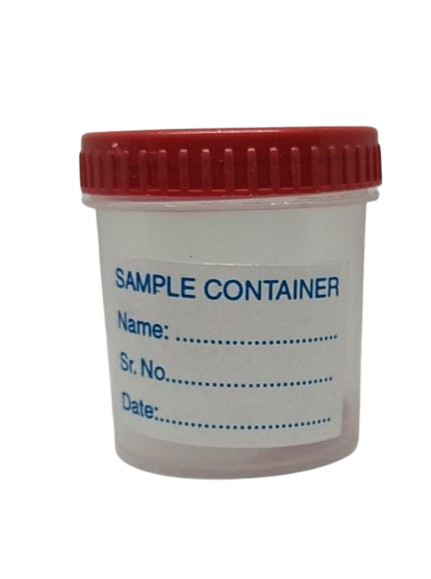

Stool Container

Stool ContainerOur ProductsFrom SurgicaveUplode:9 months ago from India